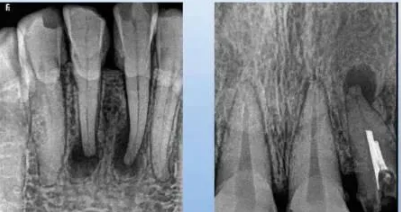

1.慢性根尖膿腫

病理及臨床:根尖部膿液被纖維組織包圍,或由根尖肉芽腫得中央細(xì)胞壞死、液化形成。多無(wú)自覺癥狀,時(shí)有齦瘺。

X線表現(xiàn):根尖區(qū)邊界不清楚但不銳利的透射區(qū),密度不規(guī)則。

2.根尖肉芽腫

病理及臨床:致密的結(jié)締組織包繞根尖的肉芽組織。常無(wú)癥狀,咬合無(wú)力,牙伸長(zhǎng)感。

X線表現(xiàn):范圍較小,周界清晰,無(wú)致密骨壁線。